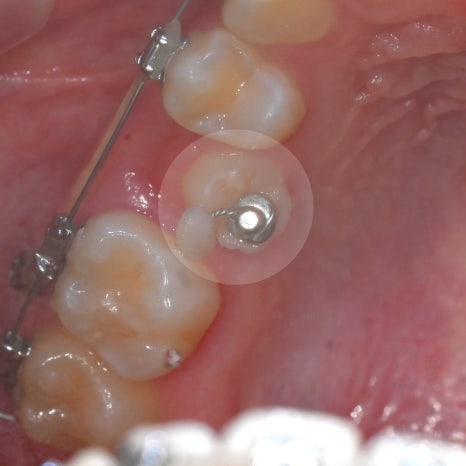

유치 발치 후 매복된 영구치(# 15번)를

맹출 유도, 정상적인 배열을 도모하여

개방교합을 개선시키고

정상적인 어금니 교합을 만드는 것을

치료의 목표로 설정하였습니다.

23.06.11 ~ 25.01.12

매복되어있던 작은 어금니가

잇몸 위로 조금씩 모습을 드러내던 과정입니다.